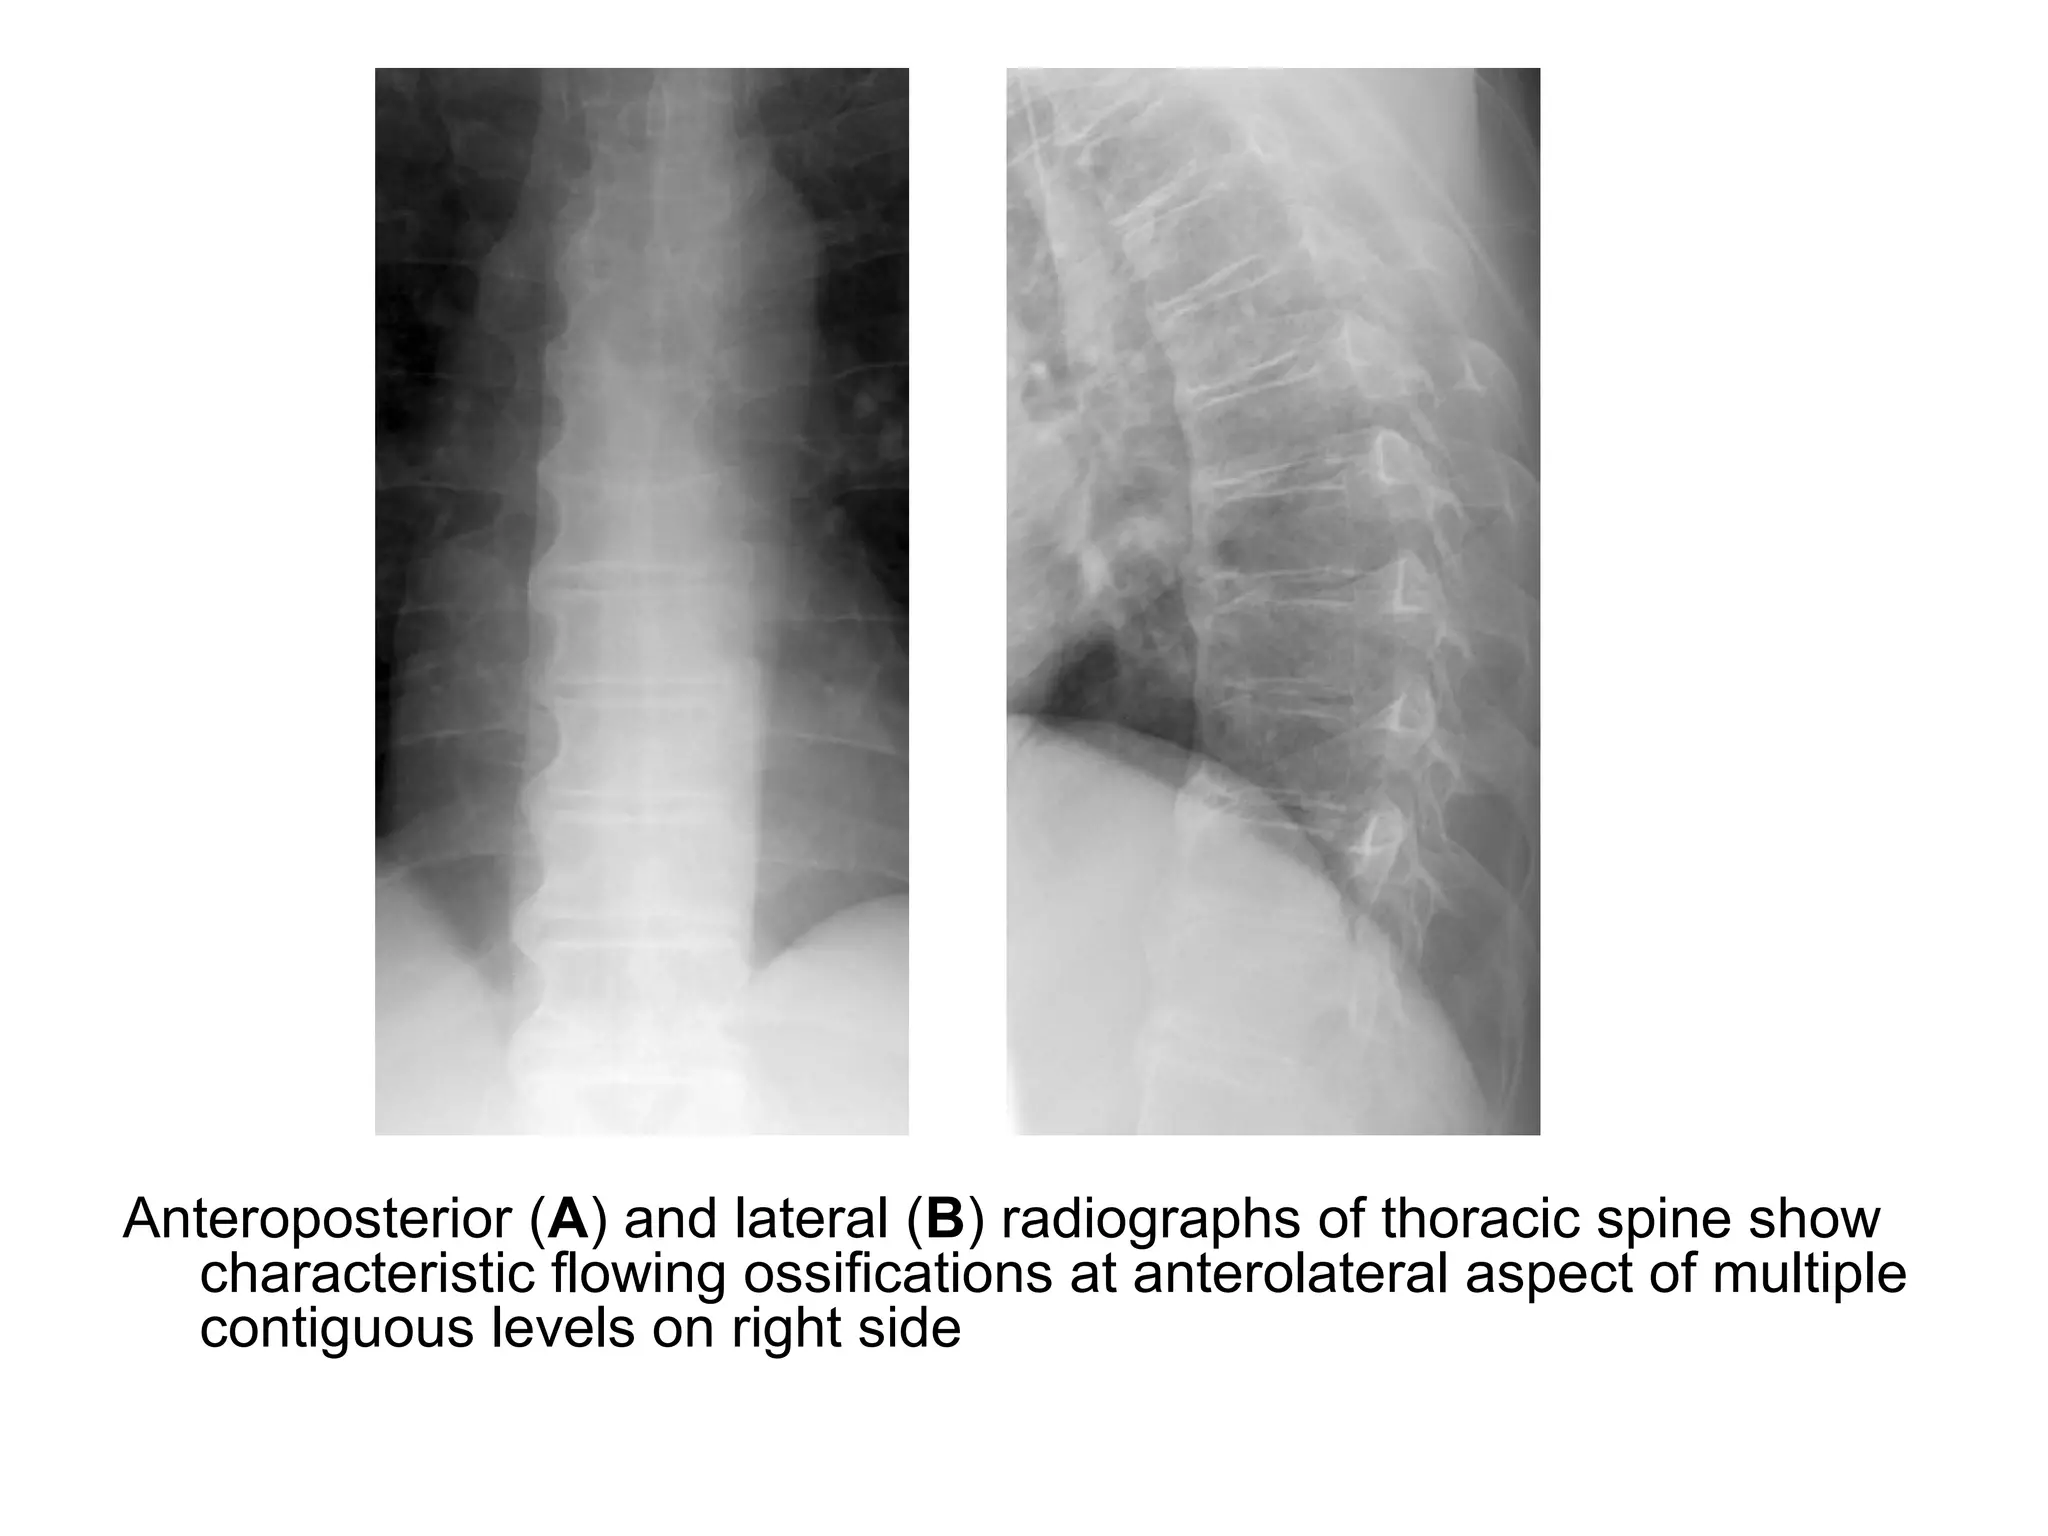

g) Diffuse Idiopathic Skeletal

Hyperostosis : (DISH)

a) Incidence

b) Radiographic Features

a) Incidence :

-Known as Forestier disease

-DISH most commonly affects the elderly

(especially 6th to 7th decades)

-Most common site is thoracic spine (T7-11)

-Severe productive bone formation in the

soft tissues around the spine resulting in

bulky flowing osteophytes

b) Radiographic Features :

-Flowing osteophytes of at least four contiguous vertebral

bodies (anteriorly, anterolaterally, predominantly right

sided)

-Preserved disk height

-Calcification of ligaments and tendons

-No sacroilitis or facet joint ankylosis

-If seen in a child, consider JRA

Anteroposterior (A) and lateral (B) radiographs of thoracic spine show

characteristic flowing ossifications at anterolateral aspect of multiple

contiguous levels on right side